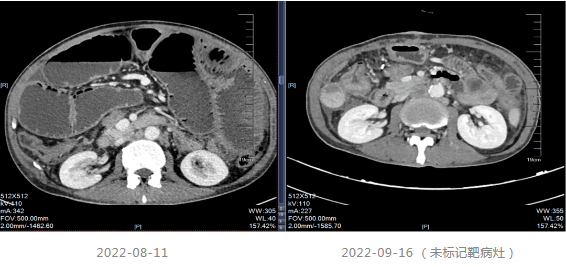

2019-03-14行上腹部增强CT,显示肝内散在的多发圆形稍低密度灶,大小不等,边界欠清晰,较大者直径约5.2cm,其内密度不均,增强扫描病灶周边有强化,内部有更低密度区液化坏死区,考虑转移瘤;胆囊多发结石;双肾多发结石,直径小于0.2cm;扫描范围内结肠肝区管壁增厚,管腔狭窄,增强扫描可见明显强化。

局部治疗:2020-09-26复查MRI提示部分病灶较前缩小,部分增大,于2020-10-22至武汉同济医院行“肝脏病灶微波消融术”,后继续口服卡培他滨至2021-5。

2021.06-01复查影像学提示肝胃间隙及腹膜后淋巴结较前增大,疗效评价PD。